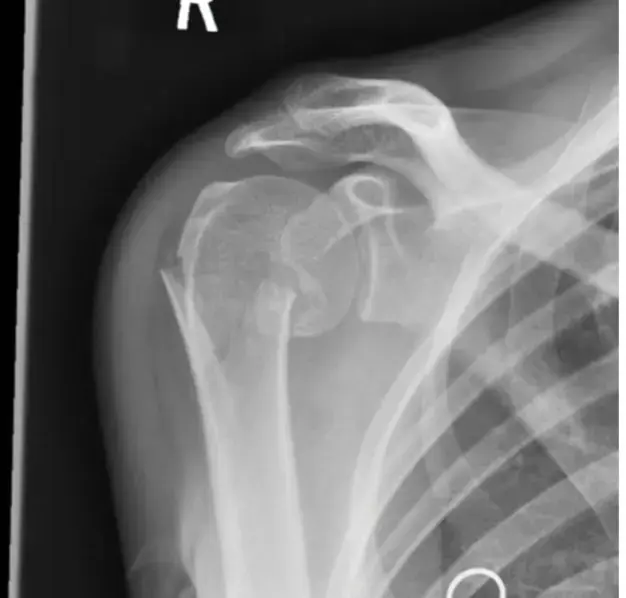

الأشعة السينية (X-rays):

- هي الخطوة الأولى والأساسية في التشخيص. يتم أخذ صور بالأشعة السينية من عدة زوايا (أمامية خلفية AP، جانبية Lateral، وربما مائلة Oblique) للكوع المصاب.

- تساعد الأشعة السينية في تأكيد وجود الخلع وتحديد اتجاهه (خلفي، أمامي، جانبي).

- الأهم من ذلك، أنها تكشف عن أي كسور مصاحبة للعظام، مثل كسور رأس الكعبرة، أو النتوء الإكليلي للزند، أو النتوء المرفقي، أو اللقمتين. وجود هذه الكسور يحول الخلع البسيط إلى خلع معقد ويؤثر بشكل كبير على خطة العلاج.

- يتم التقاط صور بالأشعة السينية قبل وبعد عملية الرد (Reduction) للتأكد من أن المرفق قد عاد إلى مكانه الصحيح وأن الثبات قد تحقق.